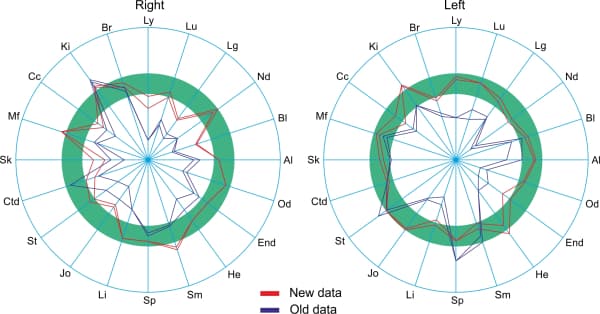

Test subject’s circular charts before the Aires Defender (Fig. 3) and after the Aires Defender (Fig. 4):

The blue line is the left side. The green line is the right side. The red dashed line is the generalized measurement.

Before using the Aires Defender, a pronounced asymmetry of the circular charts was observed due to the depression of some meridians and the activation of others.

After the effect, the chart’s asymmetry was substantially reduced and the majority of the measures were in the normal range (green band).